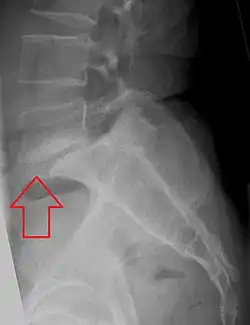

X-ray of the lateral lumbar spine with a grade III anterolisthesis at the L5-S1 level

• Grade III: 50–75%